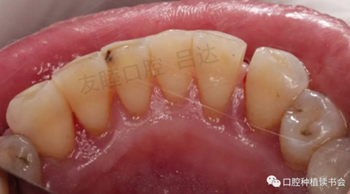

(5)首先使用25μm甘氨酸及Nozzle噴嘴進(jìn)行齦下噴砂,PEEK(聚醚醚酮)超聲工作尖清除黏膜下的牙石,局部使用抗菌肽2周。主訴部位處理后,預(yù)約患者進(jìn)行系統(tǒng)牙周治療。包括菌斑染色,齦上噴砂,齦下噴砂,超聲及手工刮治,指導(dǎo)患者正確使用牙線、間隙刷。(圖11-圖13)

圖11-13 首次治療過程

(6)3周后復(fù)查可見:1|12種植體黏膜恢復(fù)為粉色,質(zhì)地變韌,探診2-3mm,無出血、 無溢膿。(圖14)